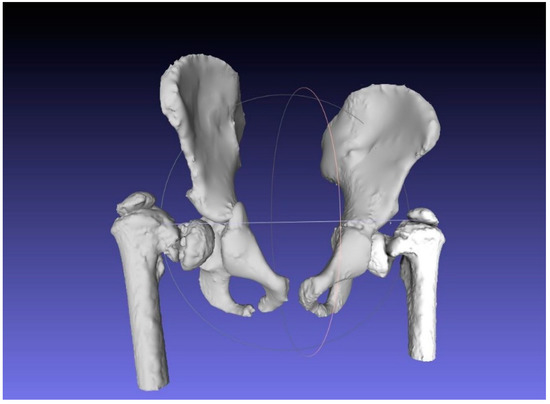

2.1. Case Study

2.2. CAM and CAD-CAT

2.3. CASS and CCG Design